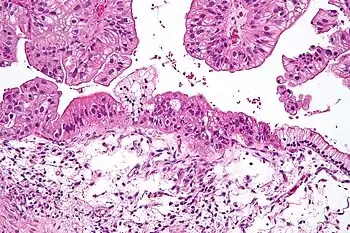

Benign mucinous tumors are typically multilocular (have several lobes), and the cysts have a smooth lining of epithelium that resembles endocervical epithelial cells with small numbers of gastrointestinal-type epithelial cells. Borderline and malignant mucinous tumors often have papillae and solid areas. There may also be hemorrhage and necrosis.

Cystadenocarcinomas (malignant tumors) contain a more solid growth pattern with the hallmarks of malignancy: cellular atypia and stratification, loss of the normal architecture of the tissue, and necrosis. The appearance can look similar to colonic cancer.

Clear stromal invasion is used to differentiate borderline tumors from malignant tumors.